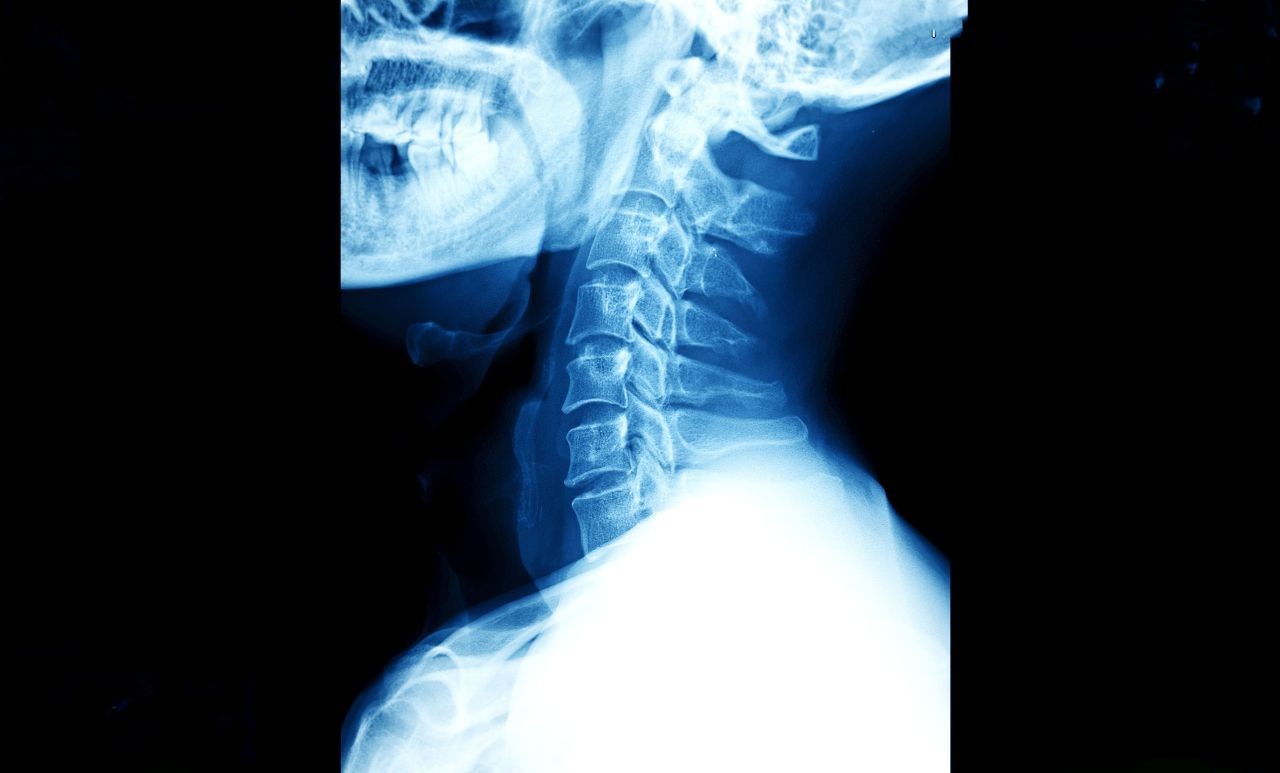

Cervical Disc Surgery: Replacement vs. Fusion for Neck Pain

If you have a herniated disc in your neck, you know the feeling: the constant ache in your neck, the electric shocks down your arm, the numbness in your fingers that makes buttoning a shirt impossible.

When physical therapy and injections stop working, surgery becomes the conversation. For decades, the "gold standard" was to fuse the bones together (ACDF). But today, active patients in New York have a better option: Artificial Disc Replacement (ADR).

At Comprehensive Orthopedic & Spine Care, Dr. Carlos Castro and Dr. Joseph Weinstein are at the forefront of motion-preserving spine surgery. We don't just want to stop the pain; we want you to keep moving your neck.